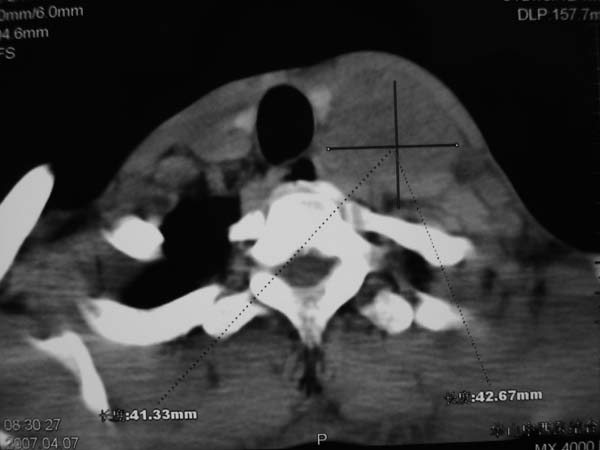

标题: CT7516[颌面颈部]:颈部病变,请会诊!

患者男性,37岁,农民,自觉左颈部肿大三天,无其它不适。

病灶边界较清,密度不均,其内可见坏死灶,左侧甲状腺受压,考虑神经源性肿瘤可能性大,建议穿刺活检。

病灶边界较清,密度不均,其内可见坏死灶,左侧甲状腺受压,考虑神经源性肿瘤可能性大。